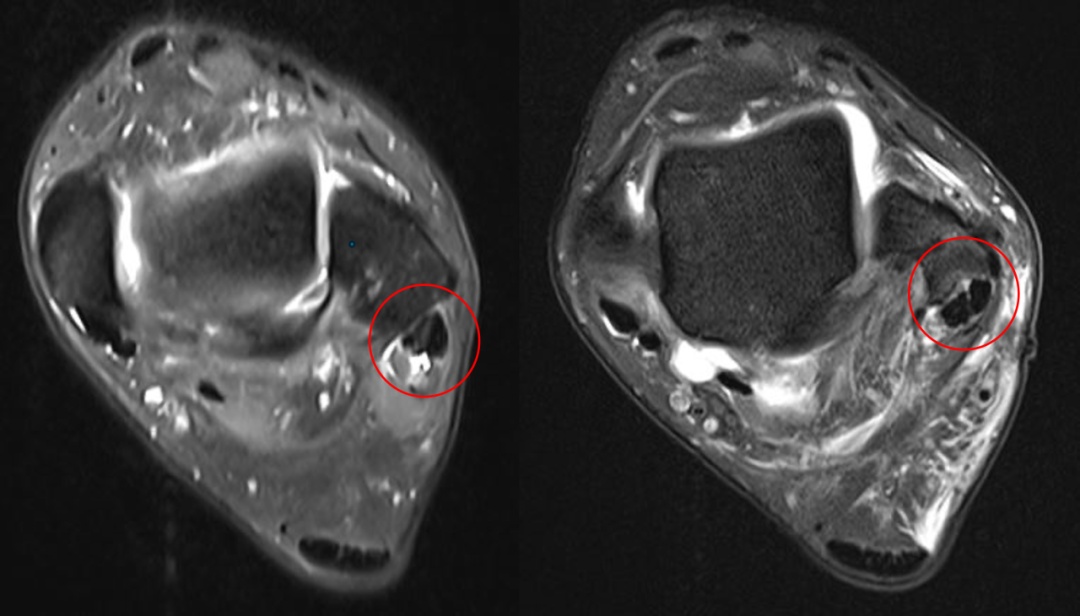

核磁共振(MRI): 能清晰显示支持带是否撕裂,以及是否有潜在的炎症。

术前检查: 典型的腓骨上支持带撕裂,肌腱处于“半脱位”状态。

图注:术前腓骨肌腱撕裂,腱沟浅平;术后MRI显示腱沟加深,肌腱已复位,原本撕裂的区域已重新固定。